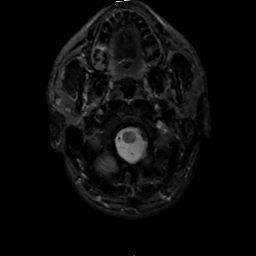

MR Study #2, February 17, 1991 -- Slice #2

[Home][Help][Clinical][Tour 1][Tour 2] Slice 2